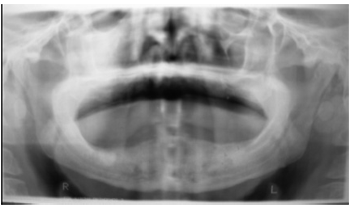

При рентгенологическом обследовании больного, на ортопантомограмме отмечается пустая лунка удаленного зуба и небольшая резорбция кости, в зоне поражения, без явных границ зоны некроза, или вы-делившихся секвестров (рис.2). На КТ снимках, кроме вышеуказанных, имеется также хронический гайморит. Был поставлен диагноз: БФОН фронтального отдела верхней челюсти справа, хронический правосторонний гайморит.